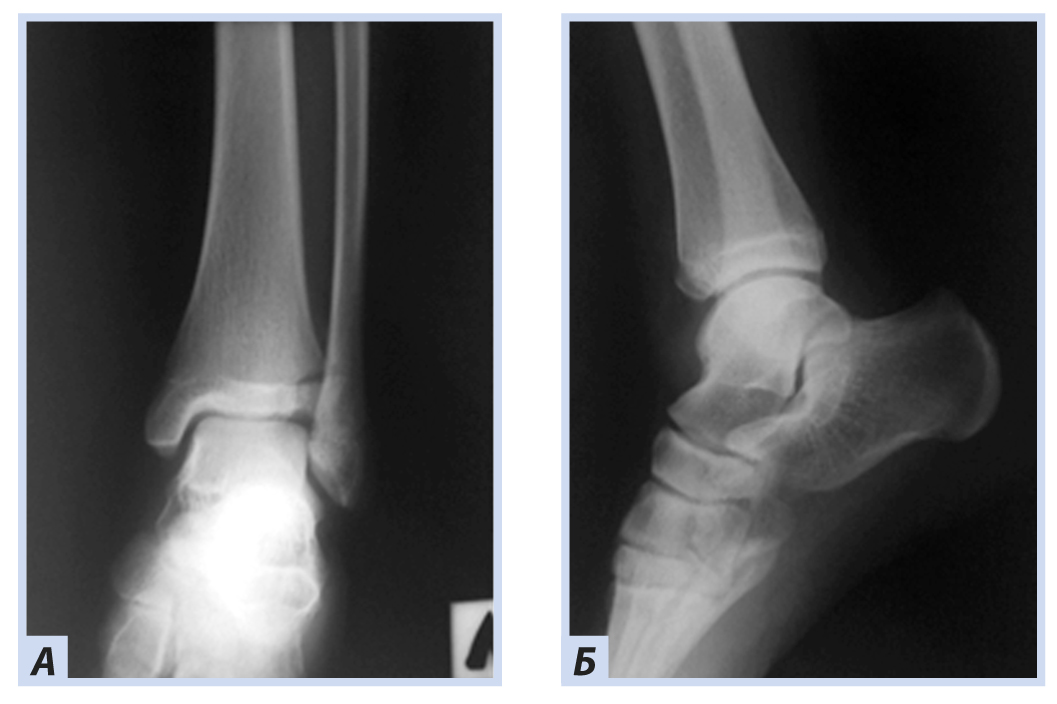

Клиническое наблюдение 3

Мальчик, 16 лет, диагноз «Закрытый перелом обеих лодыжек правого голеностопного сустава с подвывихом стопы кнаружи. Супинационно-эверсионный механизм травмы». Травма получена в результате падения на льду. По данным ультразвуковой диагностики был диагностирован частичный разрыв передней порции дистального межберцового синдесмоза. Выполнен остеосинтез внутренней лодыжки спицами, дистальный межберцовый синдесмоз фиксирован синдесмозной системой (Arthrex Tightrope Ankle), перелом латеральной лодыжки фиксирован 1/3 трубчатой пластиной. Внешняя иммобилизация осуществлена гипсовой лонгетой. Контрольная рентгенография и исследование микроциркуляции в области перелома методом лазерной допплеровской флоуметрии выполнены через 8 нед. после операции. На рентгенограммах имеются признаки зажившего перелома, по данным флоуметрии наблюдается активация капилляризации тканей и нутритивного кровотока в условиях регенераторного процесса. Спицы удалены через 8 нед., конфигурация сустава восстановлена полностью (рис. 10–13).

Рис. 10. Мальчик, 16 лет. Рентгенограммы дистального отдела костей правой голени. Перелом обеих лодыжек правого голеностопного сустава с подвывихом стопы кнаружи: А — прямая проекция; Б — боковая проекция.